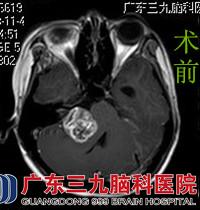

在好朋友的陪同下,丹丹来到广东三九脑科医院综合神经外科就诊。行头颅MR检查提示右侧桥小脑角区一大小约26.9*32.0*33.3mm类圆形占位性病变,鲁明主任考虑听神经鞘瘤可能性大。完善相关检查后,由鲁明主任主刀,在全麻下行右侧桥小脑角占位切除术,显微镜下见肿瘤向内听道生长,呈鱼肉样,边界清楚,质地中,血供较丰富,部分面听神经和肿瘤粘连紧密,包裹右侧面听神经和右侧舌咽神经,在电生理监测保护下予肿瘤切除,神经保留完整,手术顺利结束。术后经过治疗护理,丹丹康复出院。术后病理结果:神经鞘瘤。